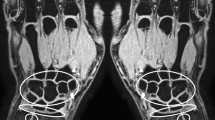

The dynamic contrast-enhanced MR images were analyzed with in-house developed software, running on Matlab [33]. Outcome measures were divided in time-intensity-curve shapes and conventional descriptive measures. Time-intensity-curve shapes represent the change in signal intensity per voxel over time. Although time-intensity-curve shapes do not provide quantitative measures, indicate tissue characteristics such as degree of vascularization, tissue viability, perfusion and volume of the interstitial space. Every voxel within the region of interest is classified independently in one of the following seven time-intensity-curve shapes with unique colors: non-enhancing (1, gray), slow enhancing (2, green), fast enhancing followed by either a plateau phase (3, blue), washout phase (4, purple) or gradual increase (5, yellow), arterial patterns (6, red) and all remaining patterns (7, white) (Fig. 2). The classification algorithm is described in detail in [21]. The time-intensity-curve shapes were then analyzed based on their relative frequency in the drawn region of interest: the number of every time-intensity-curve shape was calculated by dividing the absolute number of pixels presenting a specific time-intensity-curve shape type by the absolute total number of time-intensity-curve shapes 2-7 (i.e. all the enhancing pixels). Only time-intensity-curve shapes 2-5 were used for statistical analysis, because time-intensity-curve shapes 1, 6 and 7 are not relevant for disease activity in JIA.

Explanation of the time-intensity-curve shapes and their color coding. Time-intensity-curve shape 7 is not shown as this class includes all the various shapes that cannot be classified as 1-6. Examples are given in [21]

The relative frequency of time-intensity-curve shape 2 tended to be higher in children with inactive disease; however, this difference was not statistically significant (P = 0.150). The children with active disease showed a trend toward higher numbers of time-intensity-curve shapes 3 and 4 compared to the children with inactive disease, but did not reach statistical significance (P = 0.310 and P = 0.166). No difference between active and inactive disease was found with respect to the number of time-intensity-curve shape 5 (Figs. 4 and 5).

The difference between clinically active juvenile idiopathic arthritis in an 8-year-old boy (left) and inactive juvenile idiopathic arthritis in a 13-year-old girl (right) on maximum enhancement maps (upper row), time-intensity-curve shape maps (middle row), and T1-weighted dynamic contrast-enhanced-maps (bottom row). The colors of the time-intensity-curve shapes correspond with the time-intensity-curve shapes as mentioned in Fig. 2. Scan parameters: axial plane, echo time 6.9 ms, repetition time 9.9 ms, voxel size 1.0 mm × 1.0 mm × 1.5 mm, temporal resolution 15.5 s